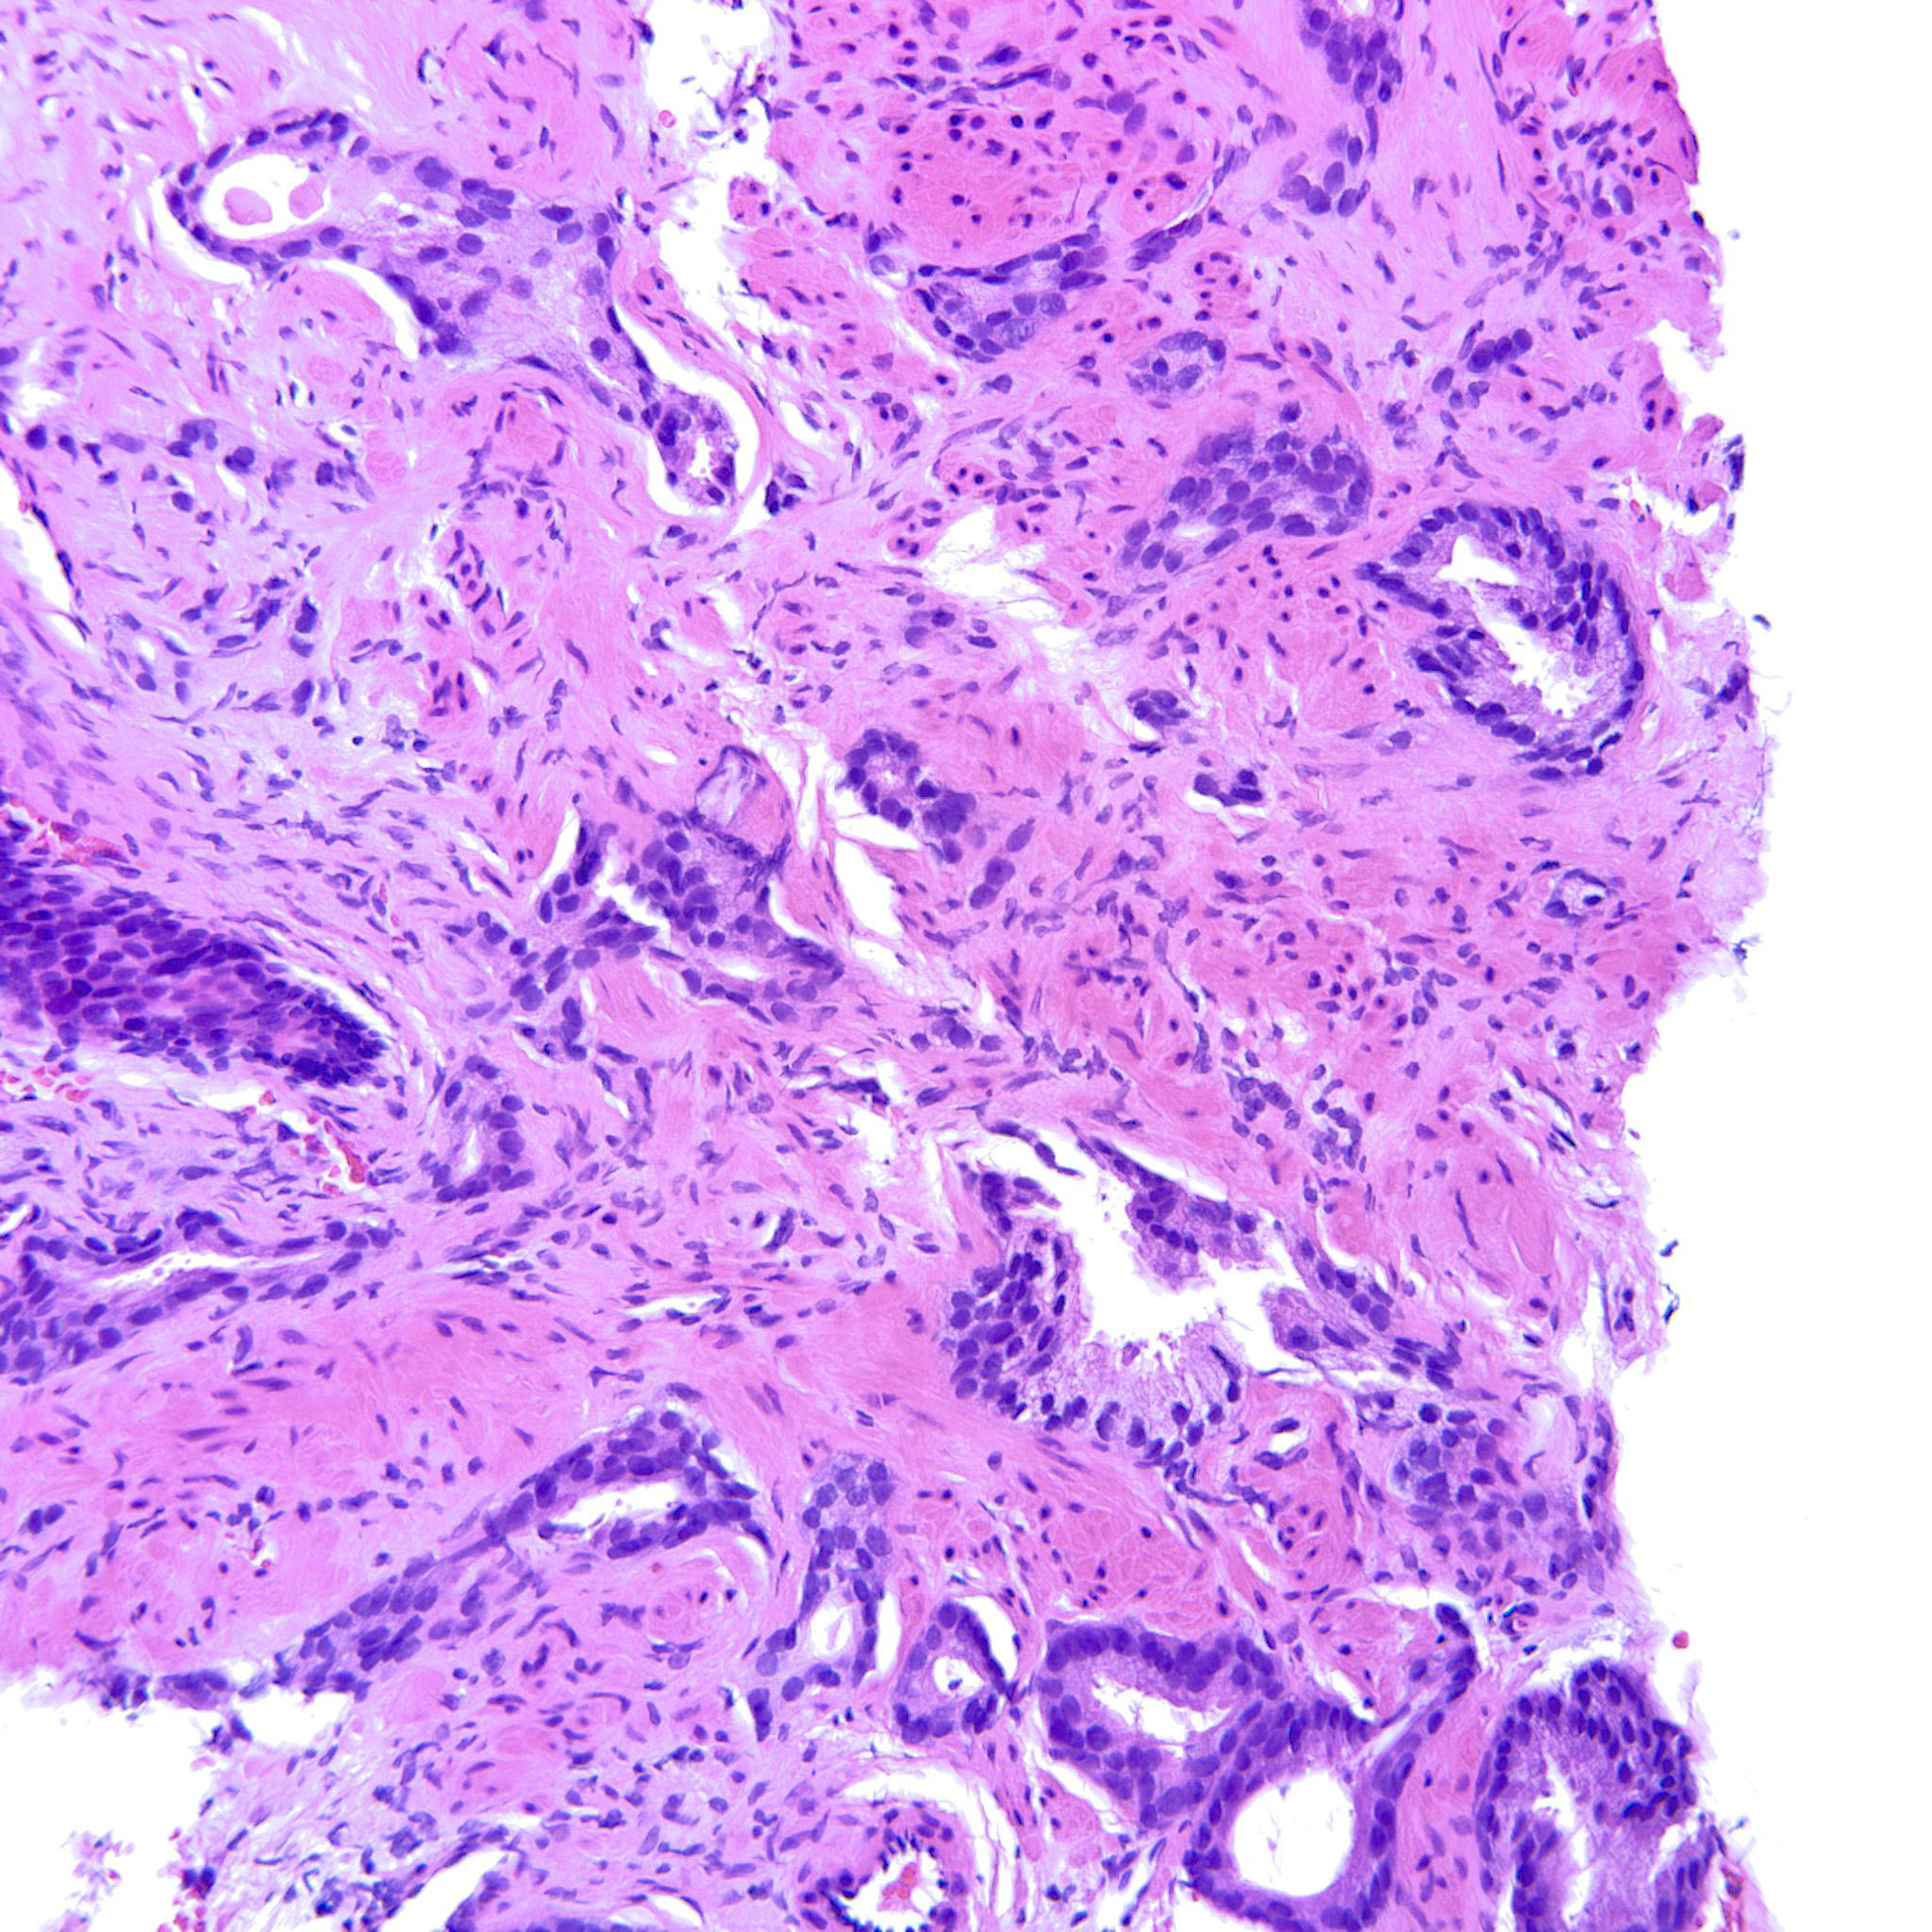

Prostate cancer grading

Case ID: 193